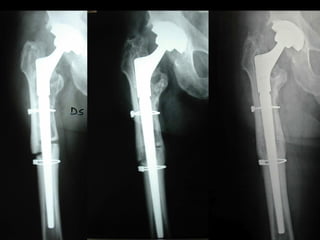

RESTORATION MODULAR

RISULTATI CLINICI (HARRIS SCORE)

-

follow-up medio 7,1 anni (5,6 – 9)

SODDISFACENTI

DISCRETI 4 (13 %), CATTIVI 1 (3 %)

25 (83 %)

- LA META’ CAMMINA SENZA APPOGGI

- NESSUN CASO DI RE-REVISIONE

RISULTATI RADIOGRAFICI

1) Buona ricostruzione ossea - 26 casi (87 %)

2) Non grande ricostruzione ossea, ma stelo

perfettamente stabile. Osteoporosi – 4 casi (13%)

3) Chiara mobilizzazione, da rioperare - 0